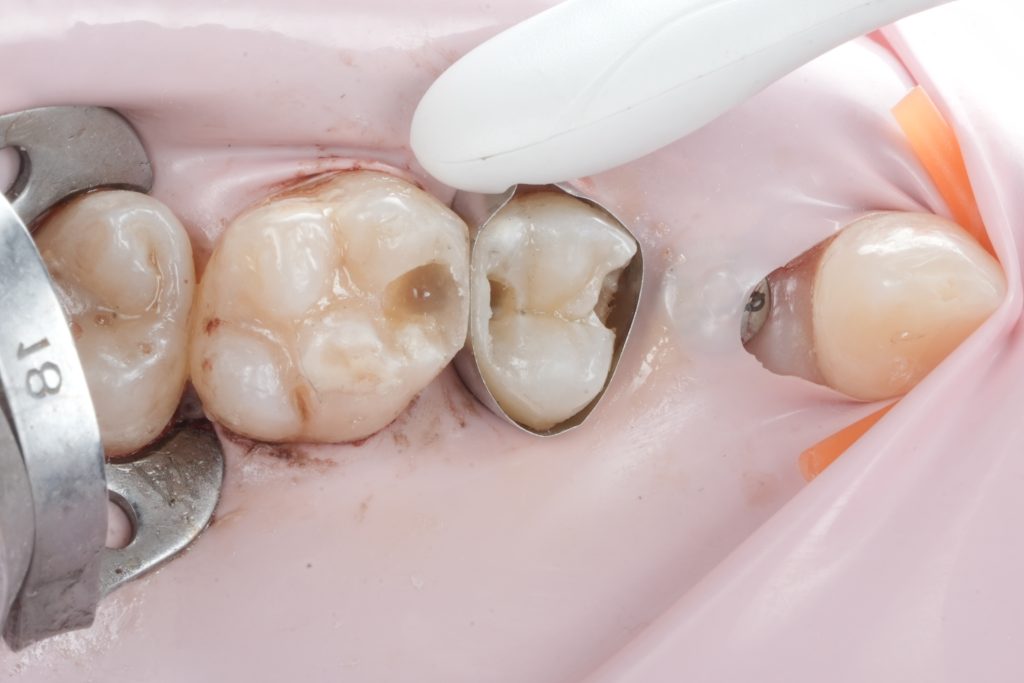

Images to place

- Fig. 5: Prepared cavity occlusal view.

- Fig. 6: Proximal box close-up (after caries removal).